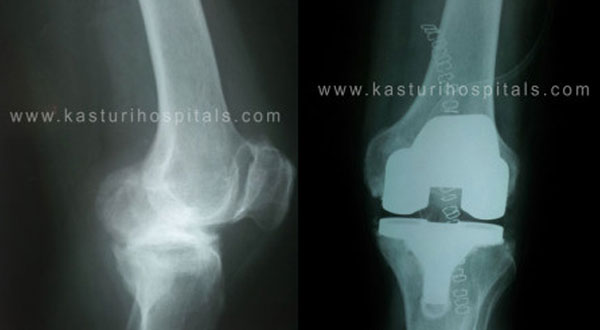

Envisaging the need for non-trauma orthopaedic care, Ortho One was founded in 2007 by Dr. David V. Rajan. Our main focus is to provide exclusive service in the sub-specialties of Sports Medicine, Arthroscopy, Joint Replacement Surgery, Paediatric Orthopaedics, Spine Surgery, Deformity Correction, etc.

Today, Ortho One Centre successfully carries out many knee and shoulder surgeries every day.We have skilled fellowship trained, and committed orthopaedic surgeons on board to deliver quality care to all our patients. Orthopaedic surgeons are confined to the above mentioned sub-specialties to give focused care. Our doctors confine themselves to one or two sub-specialties.